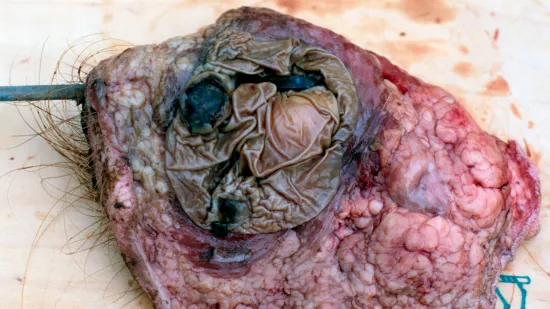

Semaine du 23-Oct-2023

Quelle est la cause de cette lésion hépatique chez une truie gestante avancée trouvée morte ?